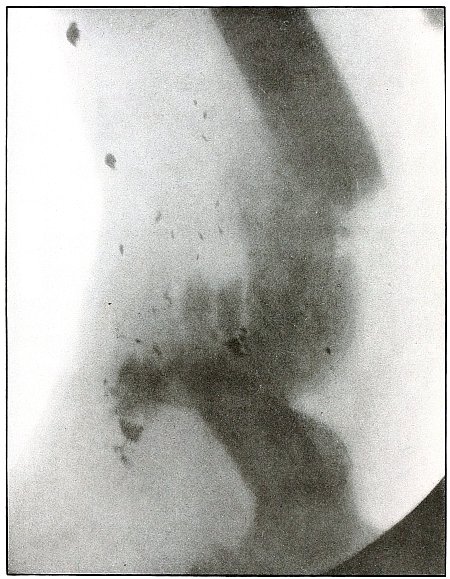

Plate 56.

[Pg 123]

Rifle—Plate 56.

LOWER EXTREMITY.

Gunshot Fracture Below the Middle of the Femur,

with Lodgment of the Bullet Near the Fracture.

The course of the projectile was transverse. The long splitting

fracture, with few large fragments and the lodged undeformed missile,

indicate that the injury to the bone was caused by the missile

striking the bone with large cross section or at an inclined angle so

that all of the remaining energy of the projectile at long range was

absorbed by the bone.

Had the point of the ball struck the bone with the same energy, it

would have produced smaller fragments and might then have passed

beyond the bone. The normal size of the diameter, slightly shortened

length, greater density of the point of the shadow, shows the bullet

to lie behind the bone with its nose pointing slightly backward. The

actual length of the bullet is 1.25 inches: the length of the shadow

is 1 inch.

Treatment and results would be about the same as in

plates 49 and 50.